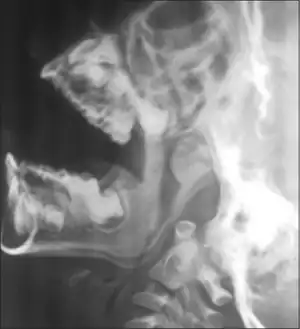

- X-ray lateral view of nasopharynx